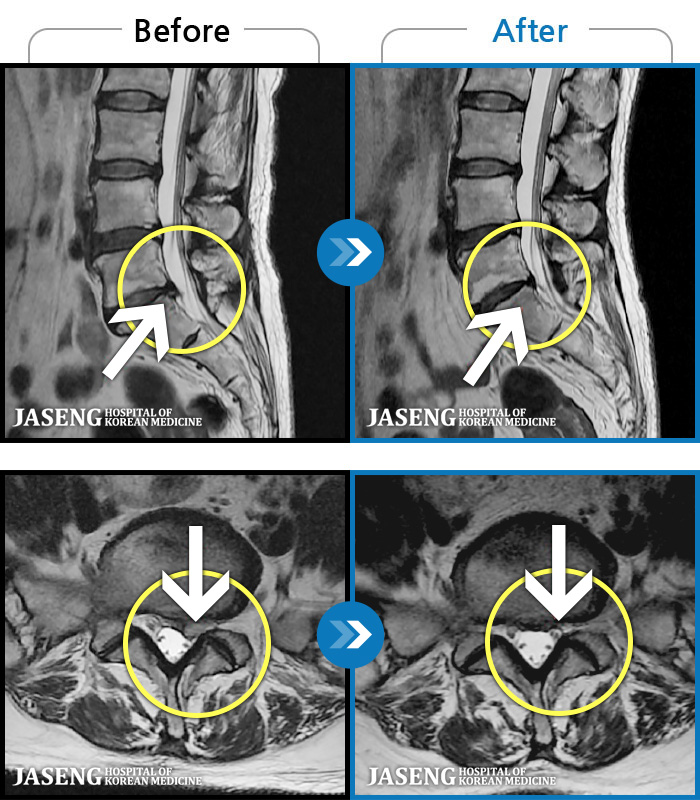

Before

After

환자에게 사전 동의를 받아 동일 조건에서 촬영되었습니다.

개인에 따라 치료 후 부작용이 발생할 수 있으니 의료진과 상담 후 치료를 진행하시기 바랍니다.

양측 허리부터 골반까지 묵직한 통증, 우측 다리 방사통이 심하여 내원하셨습니다.

아래쪽 허리와 우측 골반에 통증이 있었습니다.